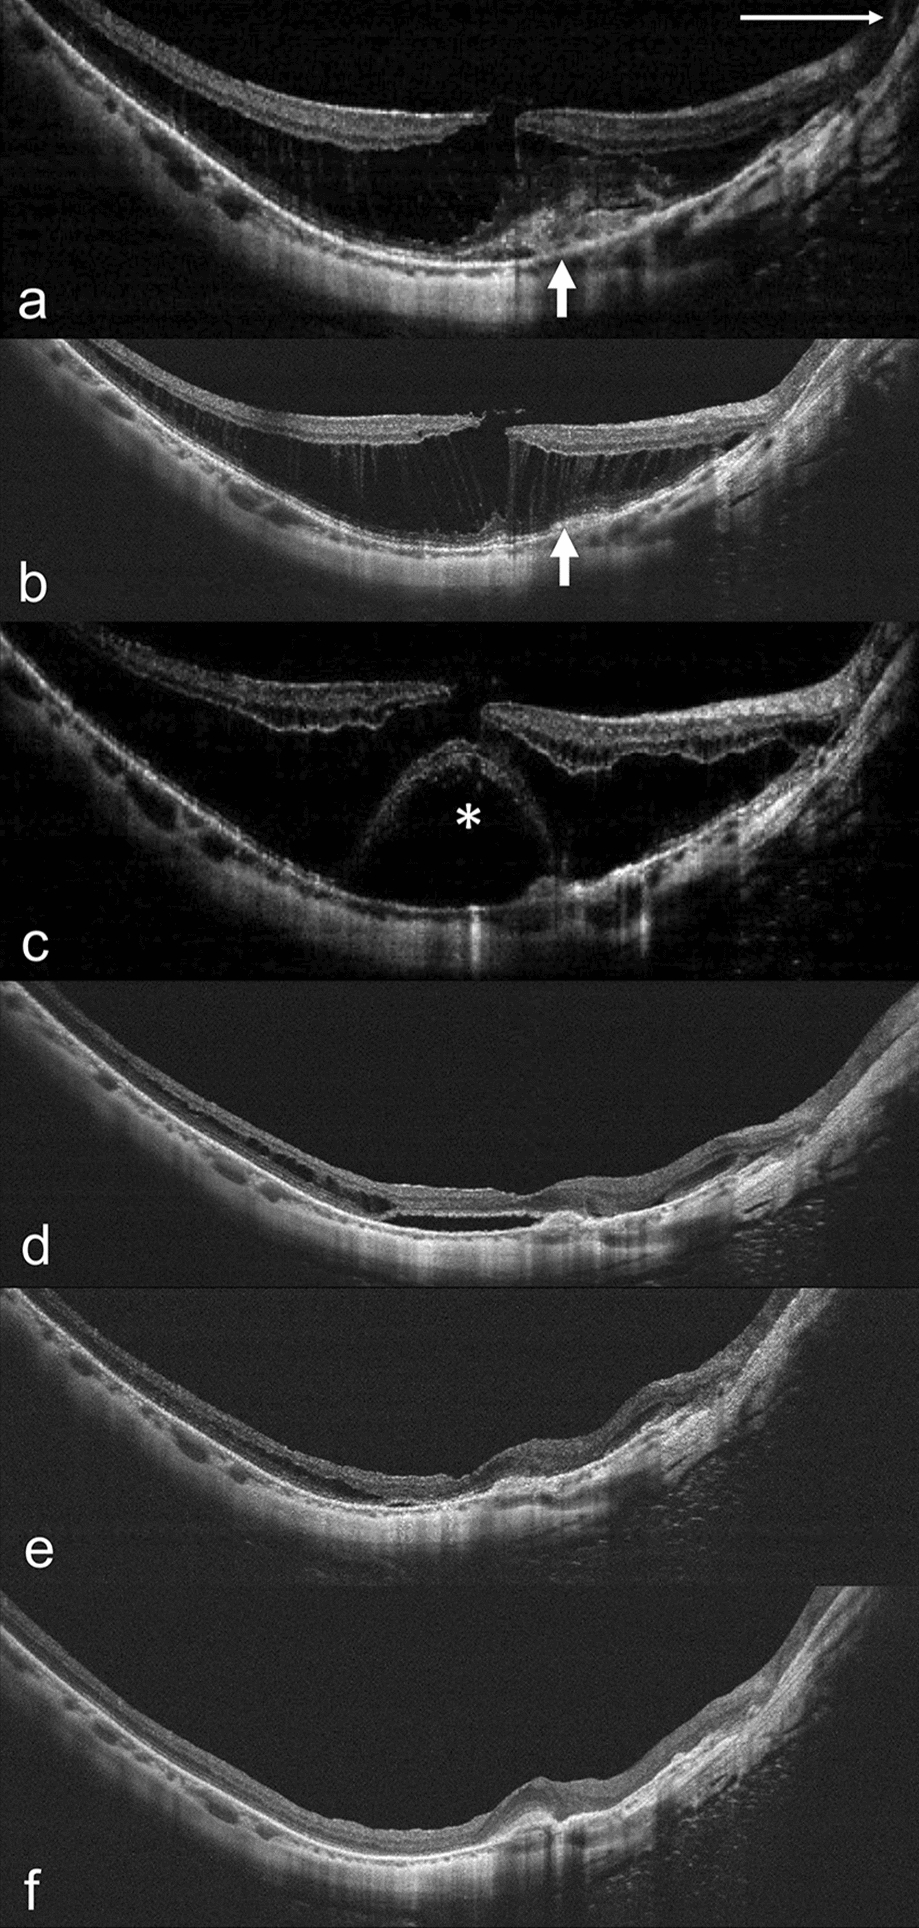

Of the 295 eyes, 13 showed progression, with 15.4% of these progressing to FTMH (1 case is shown in Fig. 1), 15.4% to FD (1 case is shown in Fig. 2), 30.8% to macular hole retinal detachment (MHRD), 7.7% to LMH, and 30.8% to other conditions at risk of vision threatening, such as foveoschisis shaped like a champagne flute [12, 13, 26] (1 case is shown in Fig. 3). Consequently, these eyes received surgical intervention at 12.7 ± 9.1 months (range 2–34 months, median 10 months) after initial injection. (Table 2). One eye (Fig. 3) received IV perfluoropropane (C3F8) [27, 28] and the other 12 eyes received pars plana vitrectomy combined with the inverted ILM flap technique [29, 30] (5 eyes; 1 case is shown in Fig. 1), the center non-peeling ILM surgery technique [3134] (3 eyes), or simple ILM peeling (4 eyes; 1 case is shown in Fig. 2). Of the 13 eyes with progression, 11 (84.6%) had MRS at baseline. Risk factors for vision-threatening MRS requiring surgical intervention in eyes with progression and onset of MRS were evaluated by using logistic regression models (Table 3). AL, AL of fellow eye, initial CFT, myopic maculopathy category at baseline, and presence of foveoschisis, inner retinal schisis, ERM, and LMH at baseline were identified to be risk factors, while intravitreal ranibizumab (IVR) and presence of retinal hemorrhage at baseline were protective factors. Eyes requiring surgical intervention compared to those with no need of surgical intervention had poorer BCVA at 1 month after injection (logMAR 0.757 ± 0.363 vs. logMAR 0.510 ± 0.410, p = 0.026), at 6 months (logMAR 0.799 ± 0.402 vs. logMAR 0.521 ± 0.451, p = 0.011), at 1 year (logMAR 0.882 ± 0.528 vs. logMAR 0.530 ± 0.413, p = 0.012), and at the last follow-up visit (logMAR 1.038 ± 0.767 vs. logMAR 0.667 ± 0.624, p = 0.030), and had greater CFT at 1 month (370.7 ± 147.5 vs. 274.9 ± 57.9 µm, p = 0.009), at 3 months (353.4 ± 129.9 vs. 268.8 ± 56.6 µm, p = 0.003), and at 6 months (415.8 ± 196.5 vs. 274.5 ± 52.1 µm, p = 0.001). In addition, the former had higher ratios of categories 3 and 4 myopic maculopathy at the last follow-up visit. We also found that there was no association of age, gender, initial BCVA, location of CNV, the number of total injections, the number of intravitreal bevacizumab (IVB), IVR, and intravitreal aflibercept (IVA) injections, as well as presence of lacquer cracks, punctate inner choroidopathy (PIC), staphyloma, MRS, outer retinal schisis, VMT, VMA, and dome-shaped macula at baseline (p > 0.05 for all) (Table 3). In eyes with MRS progression requiring surgery, the progression was found in the following ratios: 53.8% in the outer retinal layers, 23.1% presence of LMH, 7.7% in both the outer and inner retinal layers, 7.7% in inner retinal layers, and 7.7% presence of FTMH.

Fig. 3

Progression of MRS in the right eye of a 44-year-old woman with mCNV. a Before treatment, subfoveal mCNV (arrow), inner and outer retinal schisis, and posterior hyaloid membrane (arrowheads) were observed on OCT. BCVA was 20/50. b 3 months after 2 injections of IVR, mCNV became smaller (arrow) and inner and outer retinal schisis slightly increased. c 6 months after IVR, progression of outer retinal schisis to foveoschisis shaped like a champagne flute was observed on OCT. BCVA decreased to 20/100. d, e 2 weeks (d) and 1 year (e) after intravitreal injection of C3F8 0.3 ml, MRS improved. BCVA returned to 20/29 at 1 year